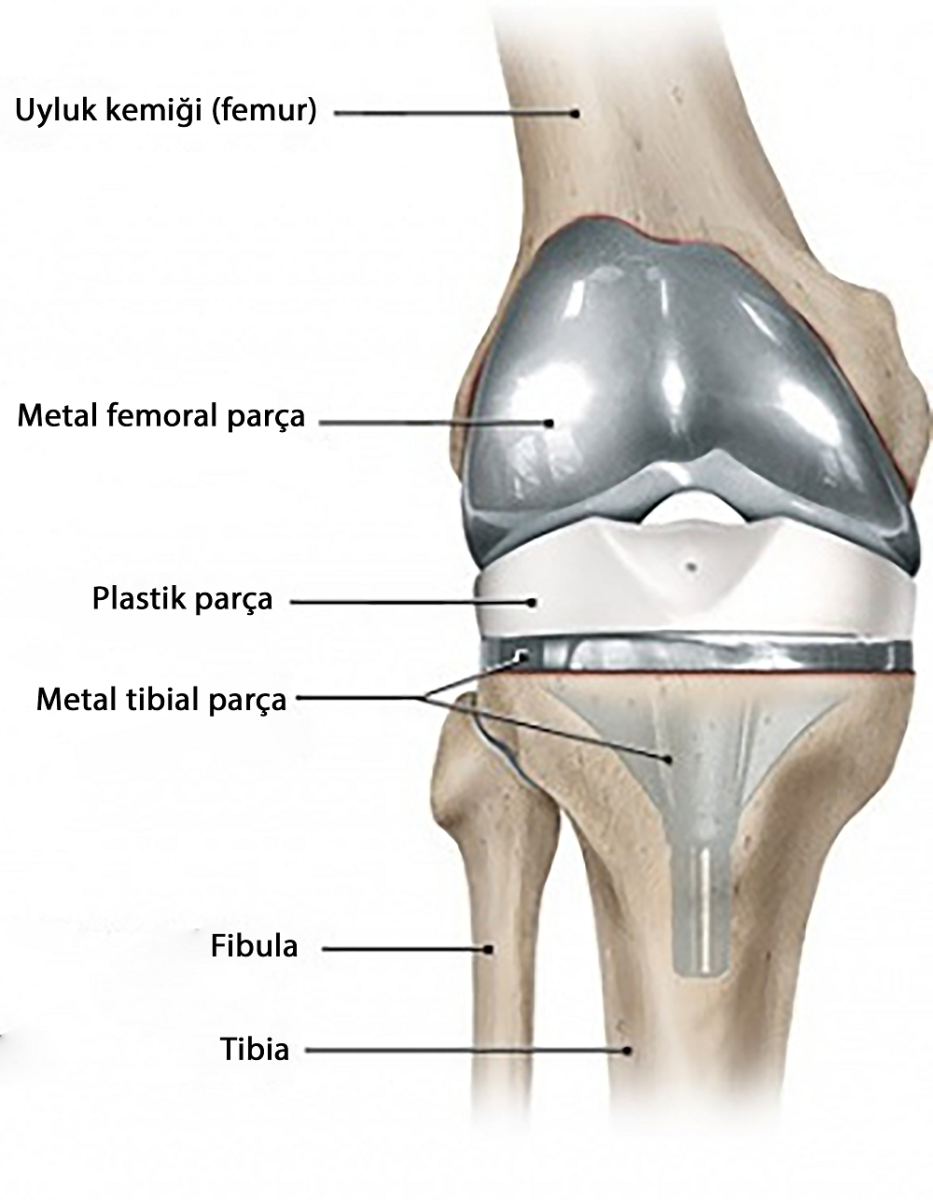

|

Total diz protezi aşınmış olan eklem yüzeylerinin, metal ve polietilenden imal edilen, ağrısız eklem hareketi için tasarlanmış özel parçalar ile kaplanarak yapay eklem oluşturulmasıdır.